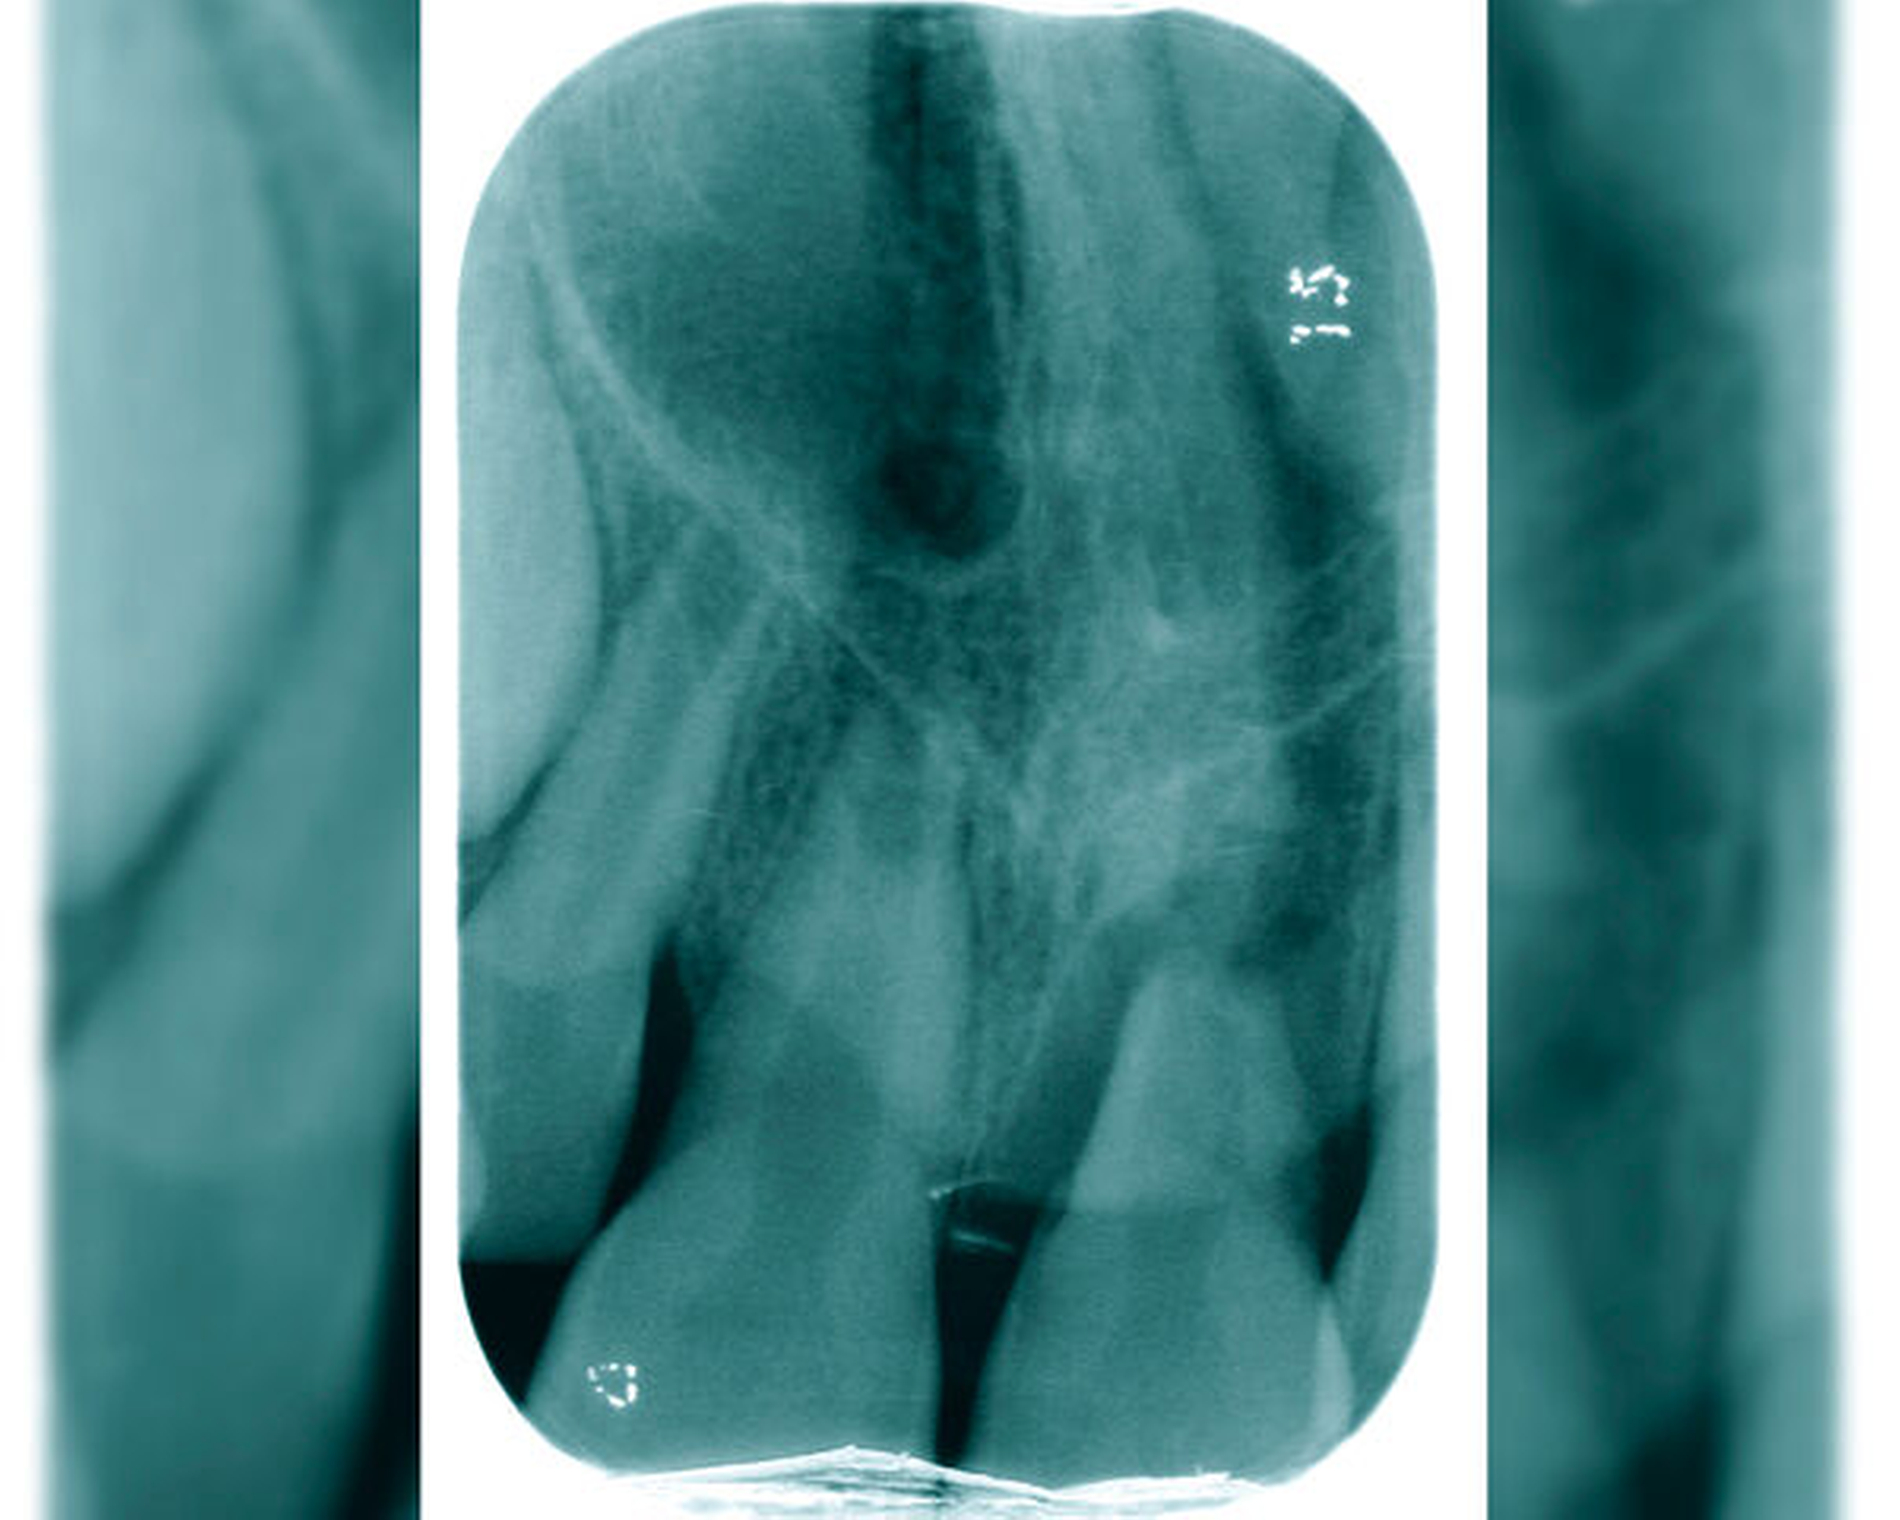

Antibiotikatherapie bei traumatisierten Zähnen

Bei einem dentalen Trauma kann es zu schweren Dislokationen der Zähne kommen. Zu den Dislokationsverletzungen gehören die Intrusion, die laterale Dislokation und die Avulsion des kompletten Zahnes als die schwerste Form der Dislokation. Bei diesen dislozierenden Zahntraumata kann von einer Verletzung oder Schädigung des Desmodonts ausgegangen werden – hier sind vor allem die Intrusion und die Avulsion der Zähne zu nennen (Abbildungen 4 und 5). In diesen Fällen wird ab dem achten Lebensjahr eine systemische Gabe von Doxycyclin zur antiresorptiven Therapie empfohlen. Die Datenlage zum klinischen Vorgehen der Antibiotikagabe ist bisher nicht eindeutig. Die Gabe des Doxycyclins beginnt am Tag des Unfalls mit einer Initialdosis von 100 mg für Patienten mit einem Körpergewicht von über 50 kg. Die Erhaltungsdosis beträgt für die kommenden sechs Tage zweimal täglich 50 mg. Kinder ab acht Jahre, die weniger als 50 kg wiegen, bekommen das Doxycyclin in einer Dosierung von 2 mg/kg Körpergewicht. Durch die kurze Gabe des Doxycylins sind Zahnverfärbungen sehr unwahrscheinlich. Des Weiteren hat bei über acht Jahre alten Patienten die Mineralisierung der Zahnkronen der ersten und zweiten Molaren bereits stattgefunden [Krastl et al., 2020] (Tabelle 2).

Ist der traumatisierte Zahn mit abgeschlossenem Wurzelwachstum um mehr als 1 mm aus der Alveole ausgelenkt worden, muss von einem apikalen Abriss des Gefäß-Nerven-Strangs ausgegangen werden. Die Regeneration der Pulpa bei einem ausdifferenzierten Foramen apicale (kleiner als zwei Millimeter im Durchmesser) ist extrem unwahrscheinlich, so dass es in diesen Fällen zu einer Pulpanekrose kommt. Über die Dentintubuli erfolgt nachfolgend bei traumatisierten Zähnen mit nekrotischer Pulpa eine bakterielle Kontamination – auch wenn die Zahnkrone intakt ist. Der Therapieentschluss über die Durchführung einer Wurzelkanalbehandlung sollte daher direkt am Unfalltag gefällt werden [Krastl et al., 2020] (Abbildungen 6 bis 9).